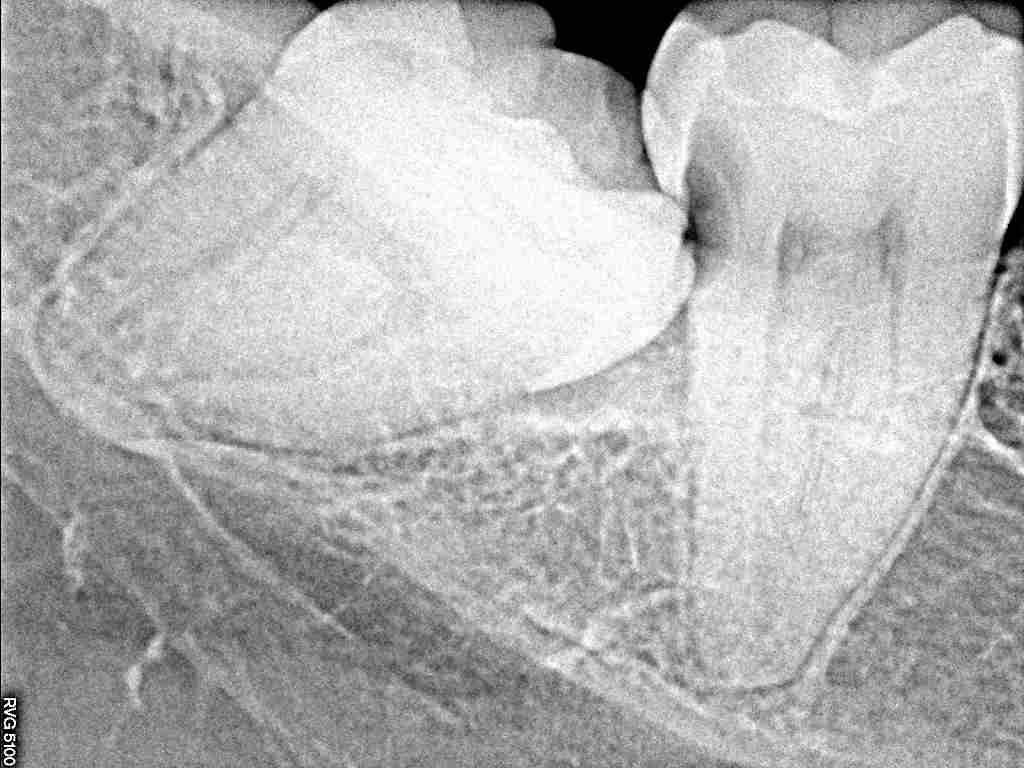

問題の歯になります

少し虫歯になっているようです

手前の歯に確かに虫歯が存在していました

少し水平埋伏歯となっています